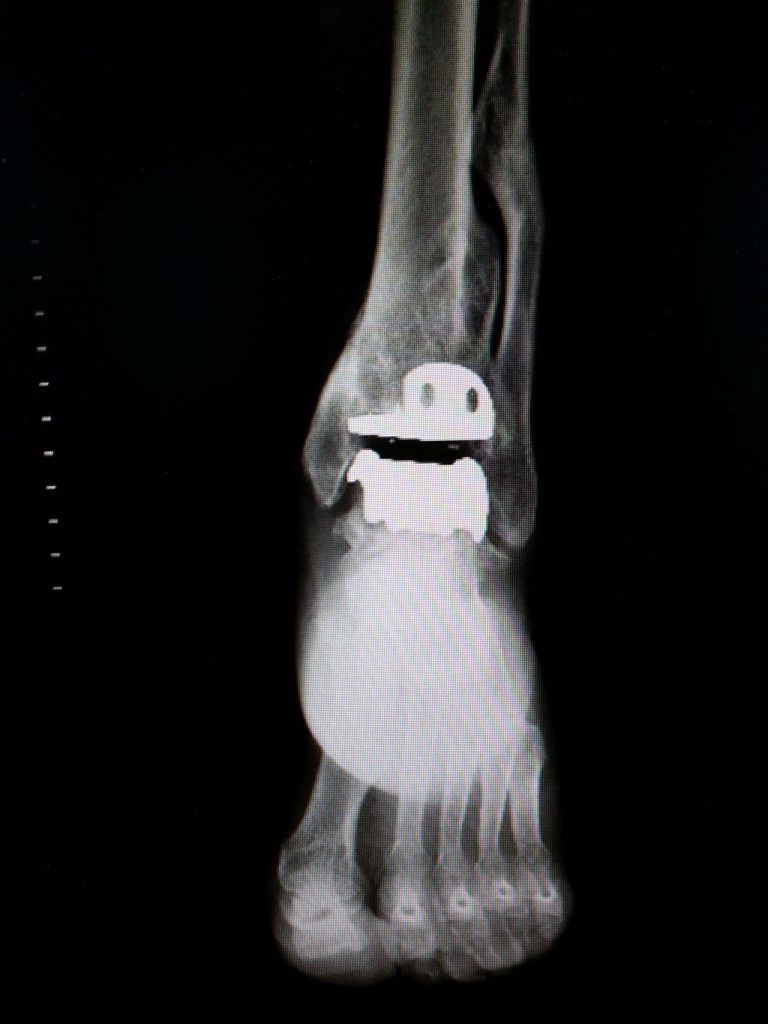

Chirurgia Protesica Mini-Invasiva

• Protesi di caviglia (mini-invasive, con carico precoce)

• Caviglia (lesioni cartilaginee, osteofiti, sinovite)